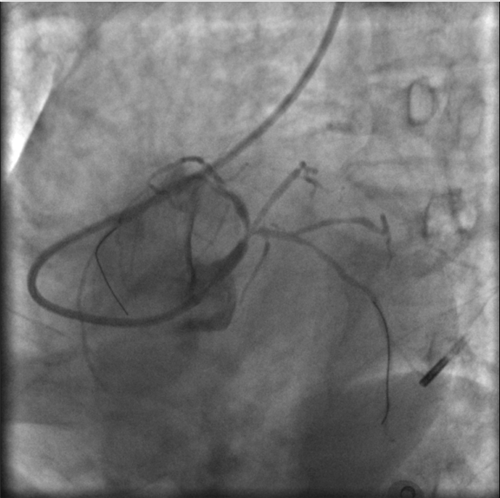

左冠血流保持通暢

確認(rèn)左冠血流保持通暢,大家懸著的心才稍稍放下。

根據(jù)IVUS檢查結(jié)果,在前降支近中段至左主干植入3枚支架,充分?jǐn)U張后,狹窄完全解除,血流恢復(fù)通暢。

植入3枚支架,血流恢復(fù)通暢